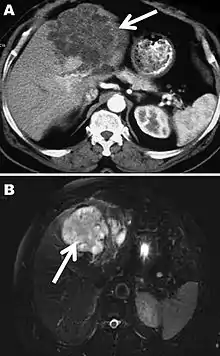

The diagnosis of polycystic echinococcosis involves isolating the protoscoleces during surgery or after the patients death in order to identify E. vogeli. Imaging, such as ultrasound and CT scans, can also be used to identify polystytic structures, but this method is not preferred as images are similar to other types of echinococcosis and liver cancer. New studies show that PCR may identify E. vogeli in the patients tissues.[5]

Disease staging